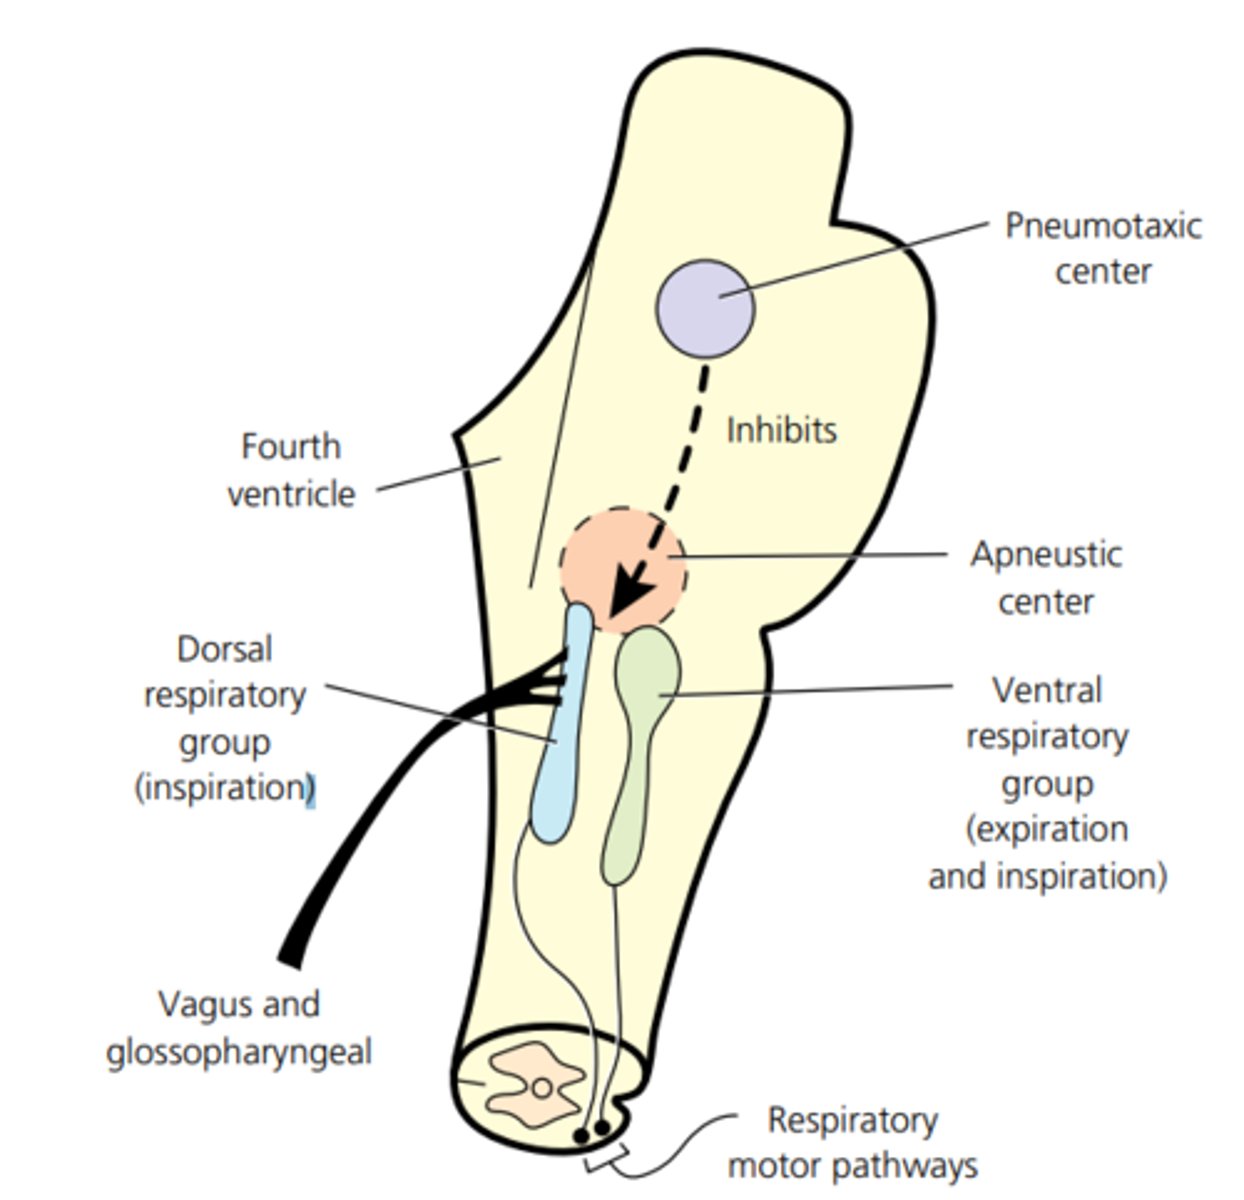

-Loose network of nuclei extending throughout the medulla, pons, and mid brain

-Contains cardiac, vasomotor, and respiratory center

Pons function

-Reticular formation in pons contains additional nuclei concerned with sleep, respiration, and posture

Central pattern generators

-Reticular formation

-Neural pools produce rhythmic signals to the muscles of breathing and swallowing